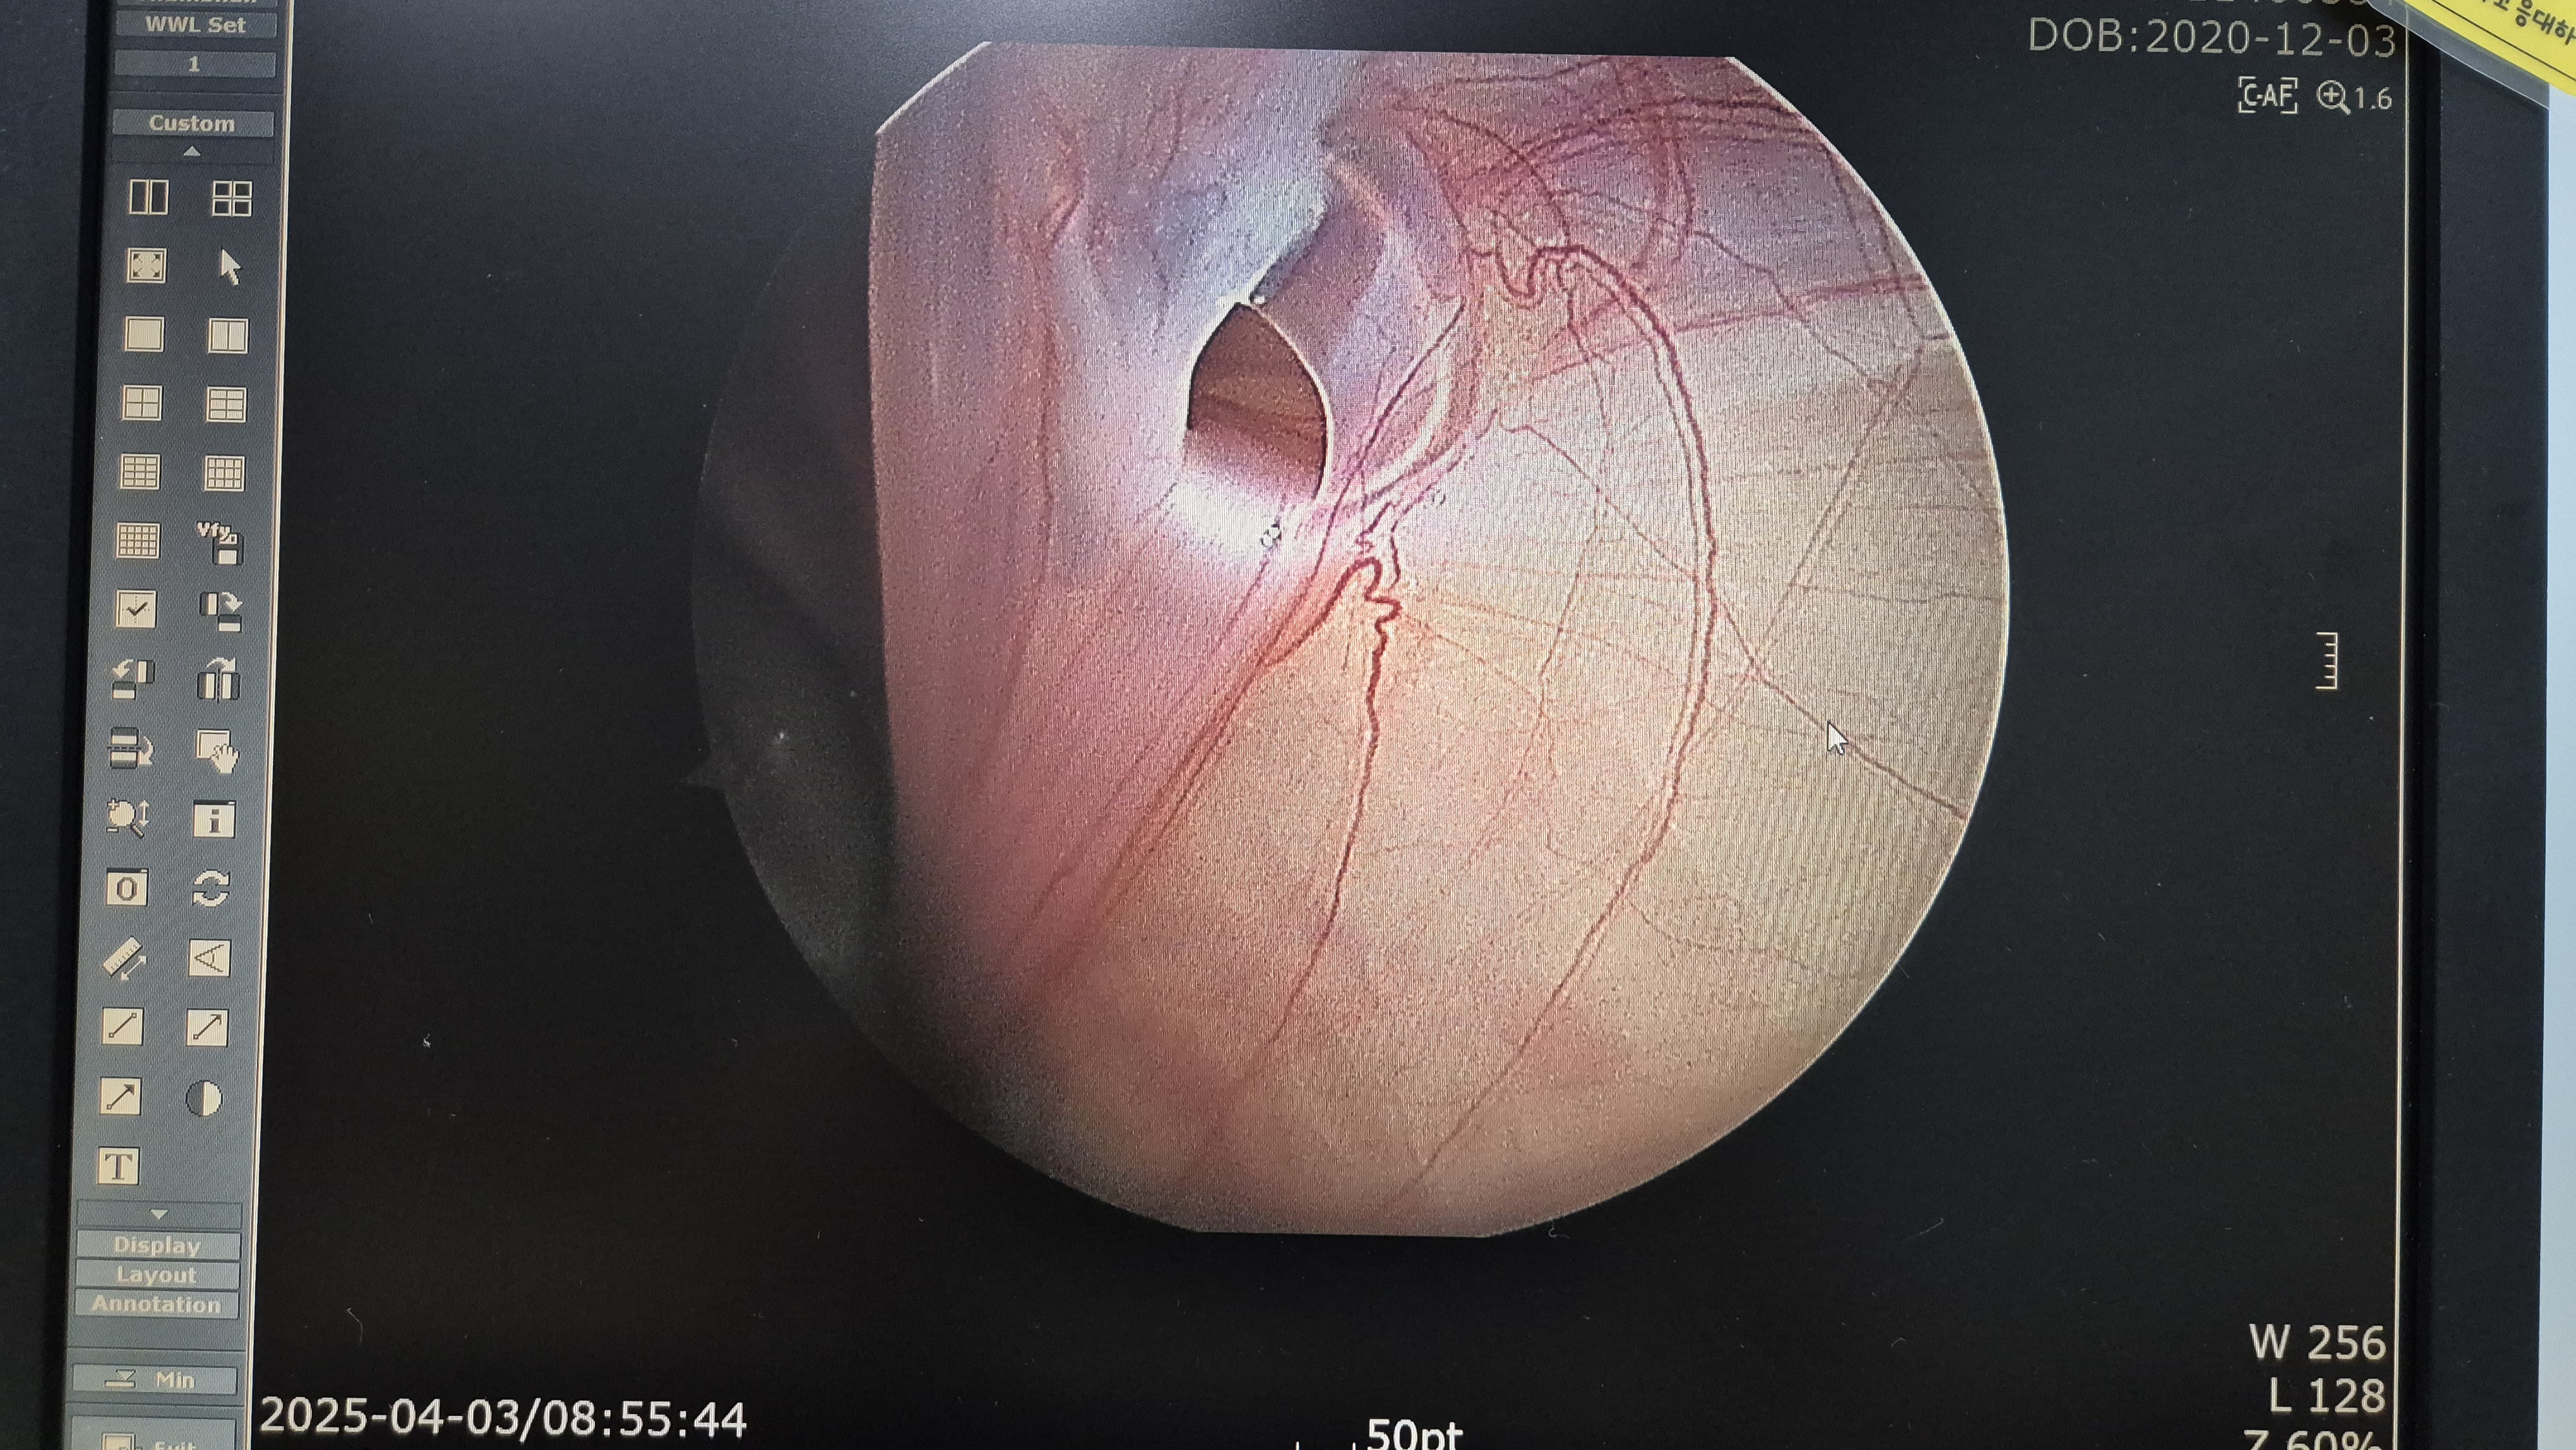

우측 서혜부 탈장.